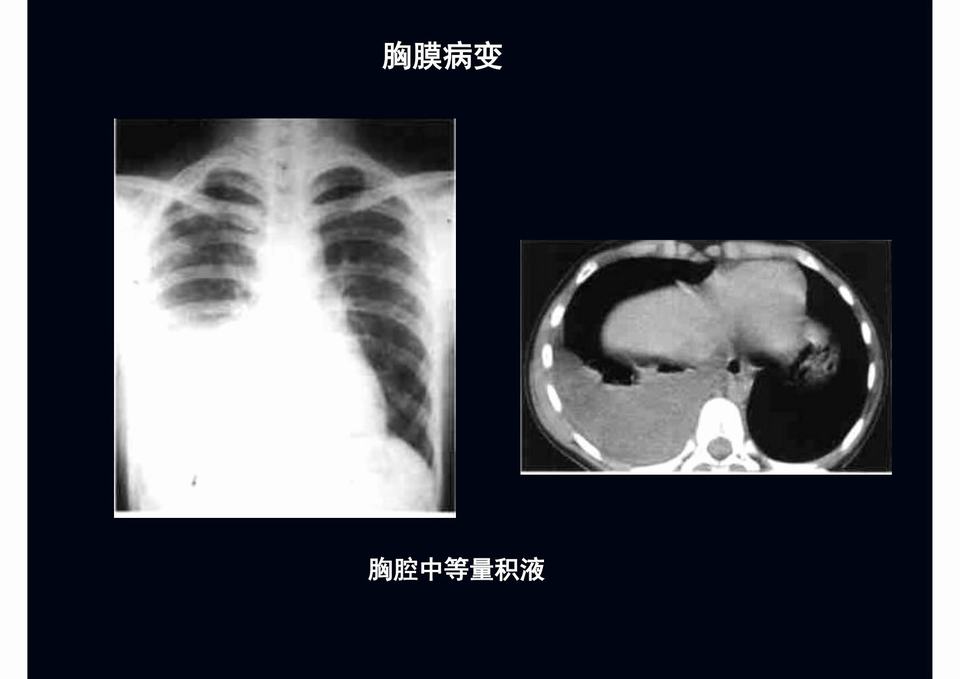

【PPT】儿童胸部影像学